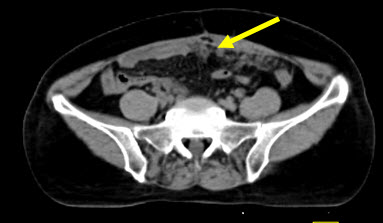

Hình 2. Bệnh nhân Lê Th. H., nữ, 58 tuổi, chẩn đoán: ung thư buồng trứng trái đã phẫu thuật và điều trị hóa chất năm 2011. Sau 8 tháng bệnh nhân kiểm tra thấy nồng độ chỉ điểm khối u CA 125 tăng cao (225ng/ml). Bệnh nhân được chỉ định chụp PET/CT kiểm tra. Trên hình PET/CT thấy tổn thương tái phát di căn màng bụng, trên hình CT không phát hiện được.